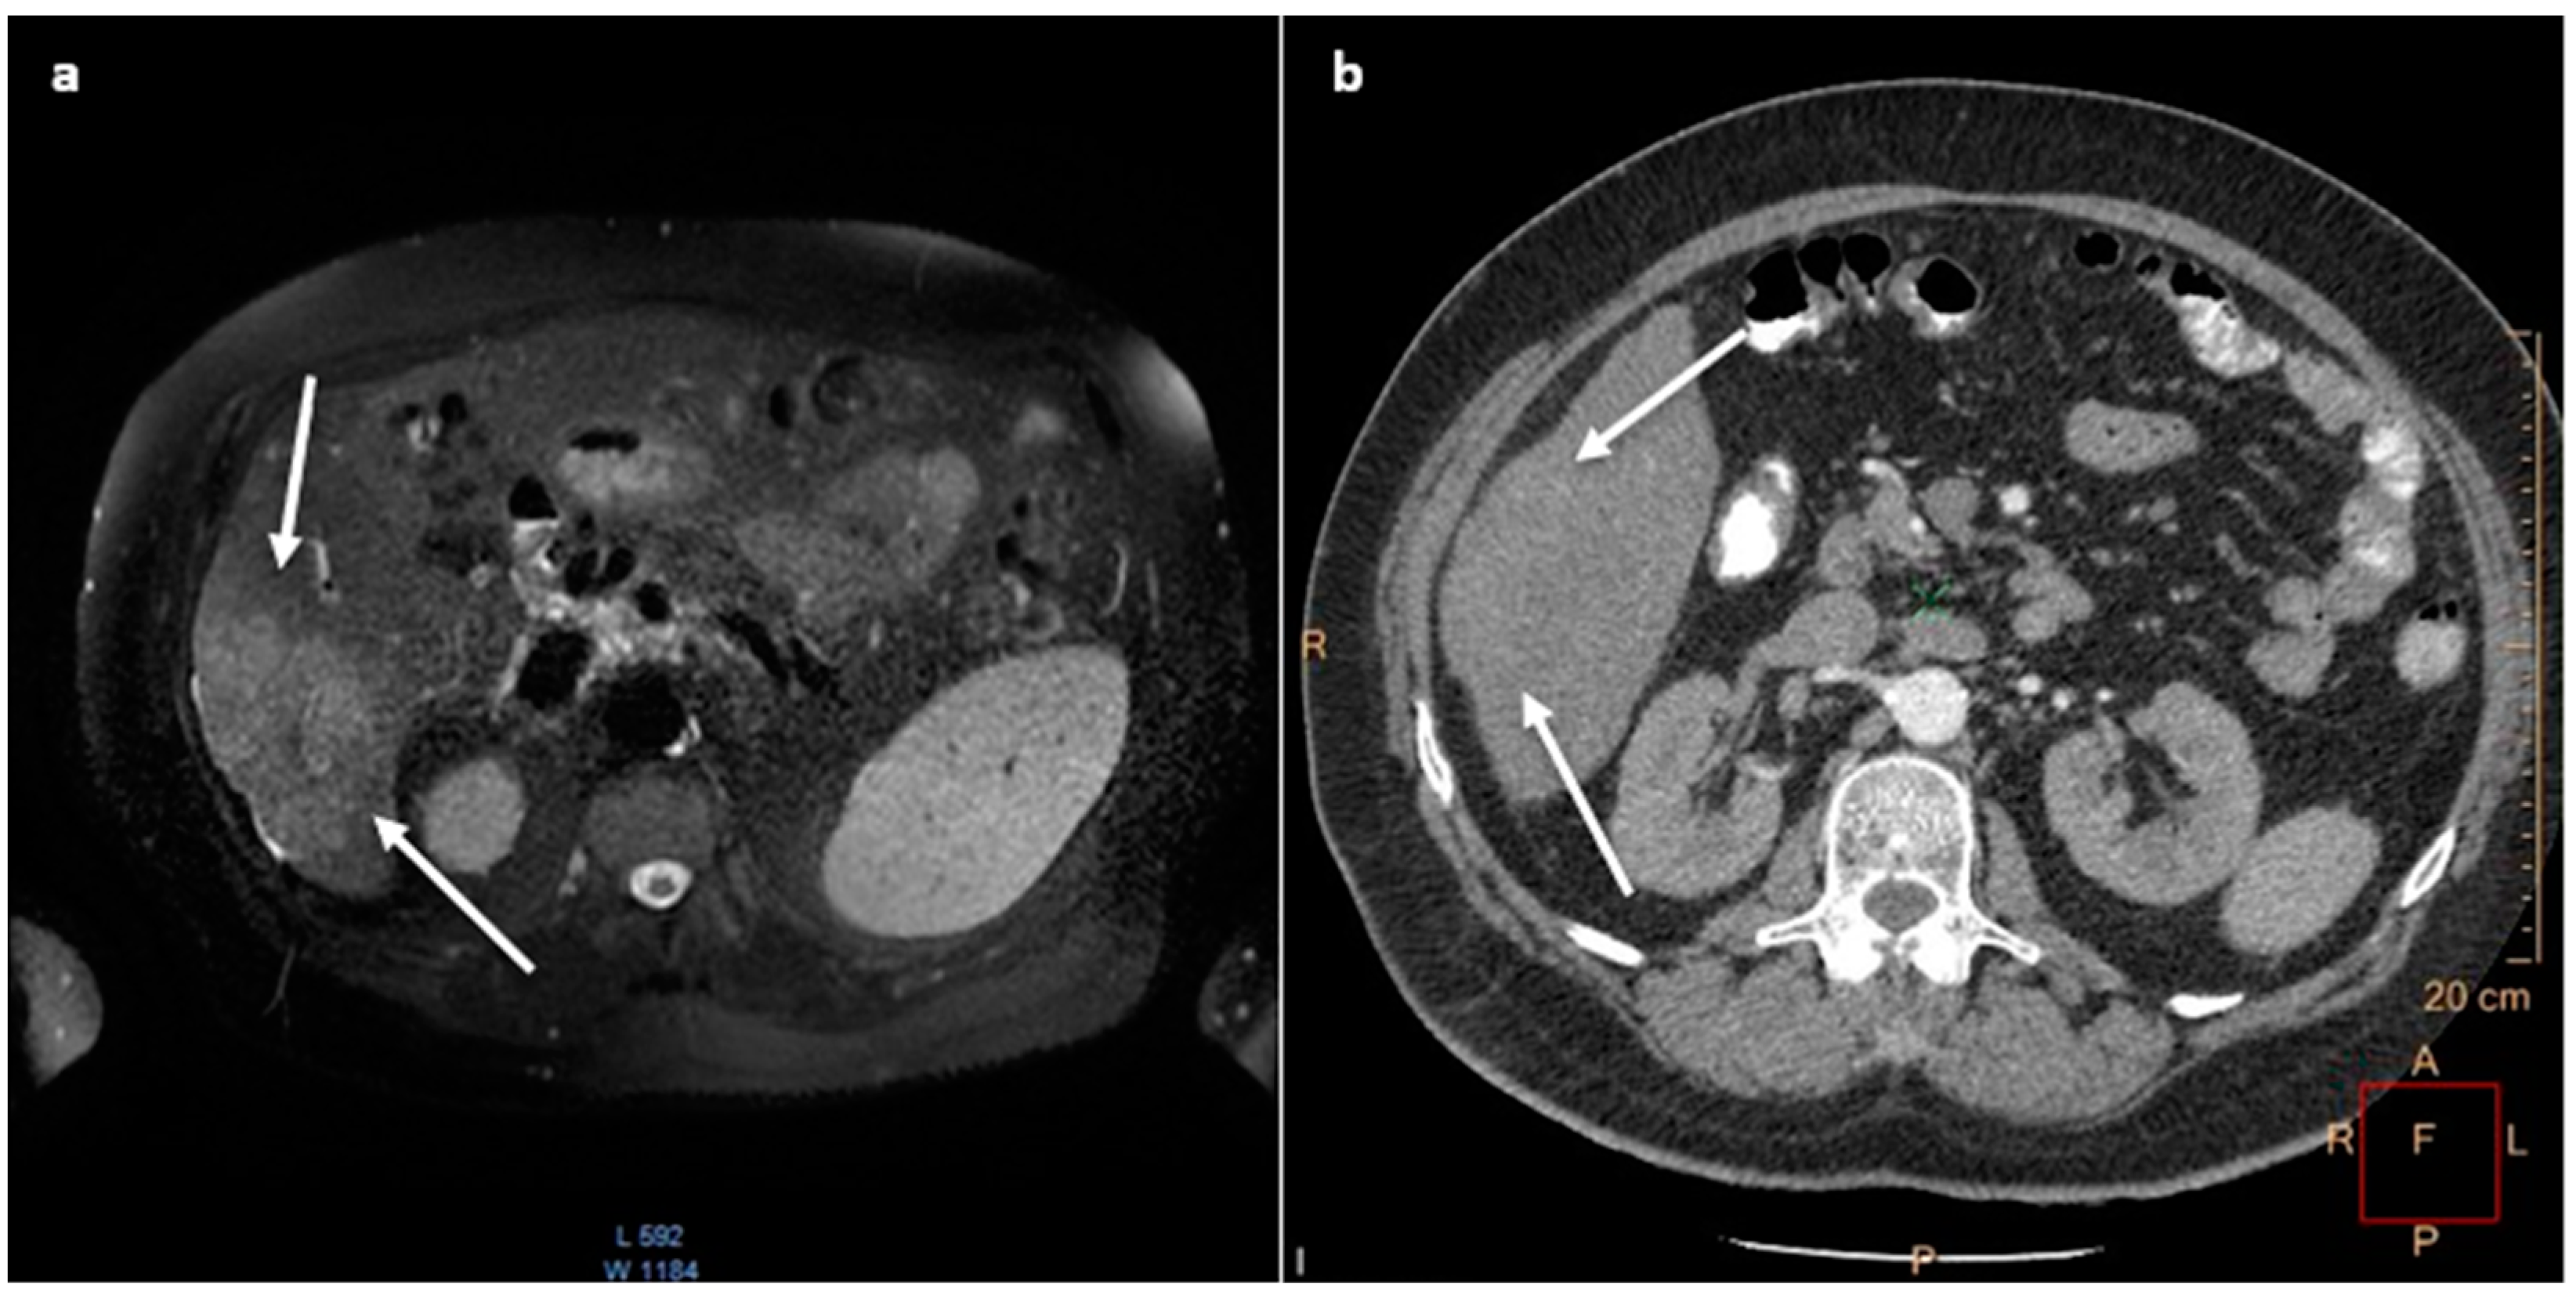

3.1. Patient I

3.2. Patient II